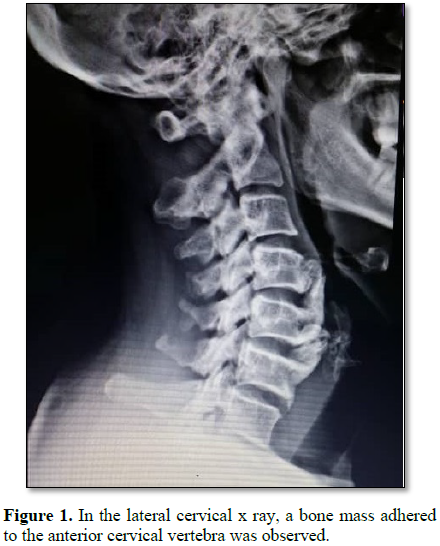

The patient was a 40 year old woman suffering from chronic neck pain and dysphagia and shortness of breath. She was under investigation and imaging to diagnose digestive and respiratory diseases and pharyngeal disease that was healthy. But in the lateral cervical x-ray, a bone mass adhered to the anterior cervical vertebra was observed (Figure 1). This patient was not obese (BMI=18.5) had no history of any rheumatoid, cardiovascular and metabolic disease and there was no evidence of disease in the studies. She did not have any neurological and motor disorder and sphincteric disorder. In the lateral cervical x-ray, a large calcified anterior ligamentous mass was observed in anterior part of body of C4, C5 and C6 vertebrae (Figure 1), causing partial obstruction of esophagus. In cervical MRI, in T1 view, isointense to hyperintense mass were observed on the anterior C4, C5, C6 and in T2 view, heterogeneous and isointense to hypointense mass was observed in the anterior cervical vertebrae (Figure 2). In thoracic spine and lumbosacral spine x-ray, bone mass was seen in anterior lumbar vertebrae (L2 and L3) (Figure 3), which had not caused any symptoms in the patient. This patient was underwent surgery and the anterior neck calcification was removed (Figure 4) and after a few days symptoms of dysphagia and dyspnea were resolved.